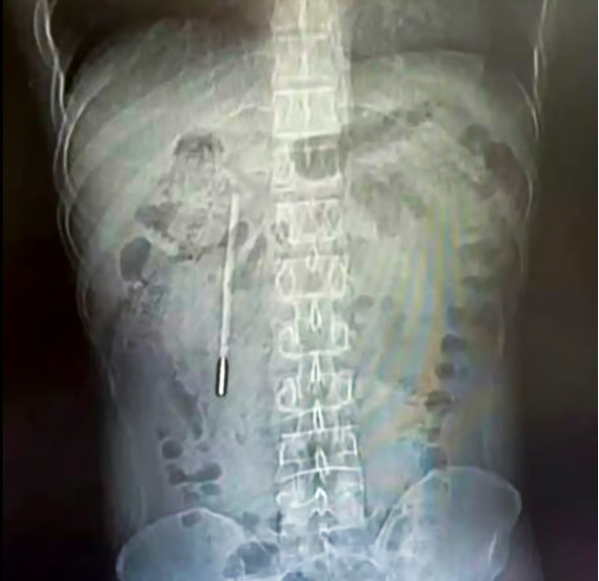

복통의 원인은 20년 전 삼킨 온도계? 중국 남성의 황당 실화

국제

• 배가 아파 병원을 찾은 32세 중국 남성의 몸속에서 수은 온도계가 발견됐어.

• 알고 보니 12살 때 실수로 삼킨 건데, 20년 동안 몸 안에 그대로 있었던 거야.

• 의사들은 20분 만에 제거 수술에 성공했지만, 정말 천만다행인 사건이지.